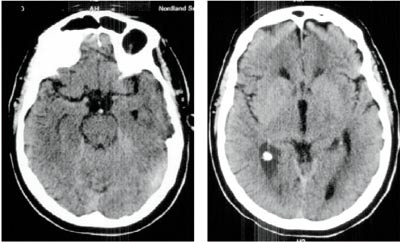

En 71 år gammel mann falt om på et offentlig sted. Han var behandlet for hypertensjon de siste fem år, den senere tid med kalsiumantagonist og angiotensin II-hemmer. Anestesilege fra sykehuset kjørte i møte med ambulansen og møtte denne etter 30 minutter. Pasienten hadde da gispende agonal respirasjon, men godt palpabelt blodtrykk og normal puls. Han ble straks intubert i pentotal-/suksametoniumnarkose og ventilert med store minuttvolum fra Lærdalsbag tilkoblet oksygen. Ved ankomst i sykehuset en time etter hendelsen var pCO₂(a) forhøyet til 10,1 kPa mens pH var 7,23 og pO₂(a) normalt. Cerebral CT tatt umiddelbart ble oppfattet som normal (fig 1). Resultatene etter undersøkelse av EKG, troponin T og CK-MB var normale. Pasienten forble dypt komatøs og ble tilkoblet respirator. Om natten, ca. 14 timer etter hendelsen, oppstod det bilateralt dilaterte og lysstive pupiller og polyuri. Pulsen falt til 30 og systolisk blodtrykk økte kortvarig fra 100 til 180 mm Hg.

Ny cerebral CT ca. 25 timer etter hendelsen viste utbredt infarsering av hjernestamme, cerebellum og begge oksipitallapper samt begynnende hydrocephalus (fig 3). Gransking av arkografiundersøkelsen viste ingen fylling av venstre a. vertebralis og bare en meget langsom fylling av sentrale deler av en tynn høyre a. vertebralis. Det var ingen kontrastfylling av a. basilaris (fig 2).